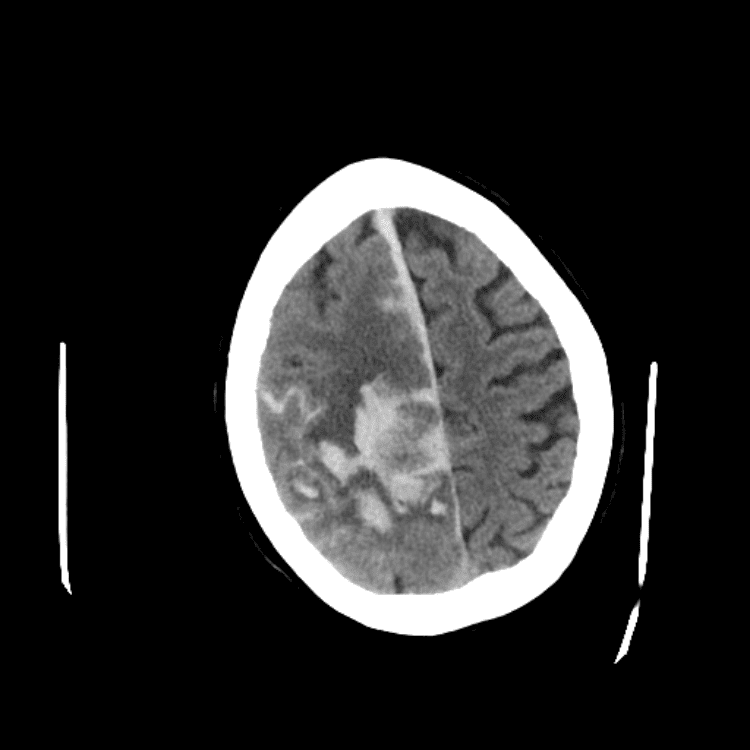

Nontraumatic Brain

Classic